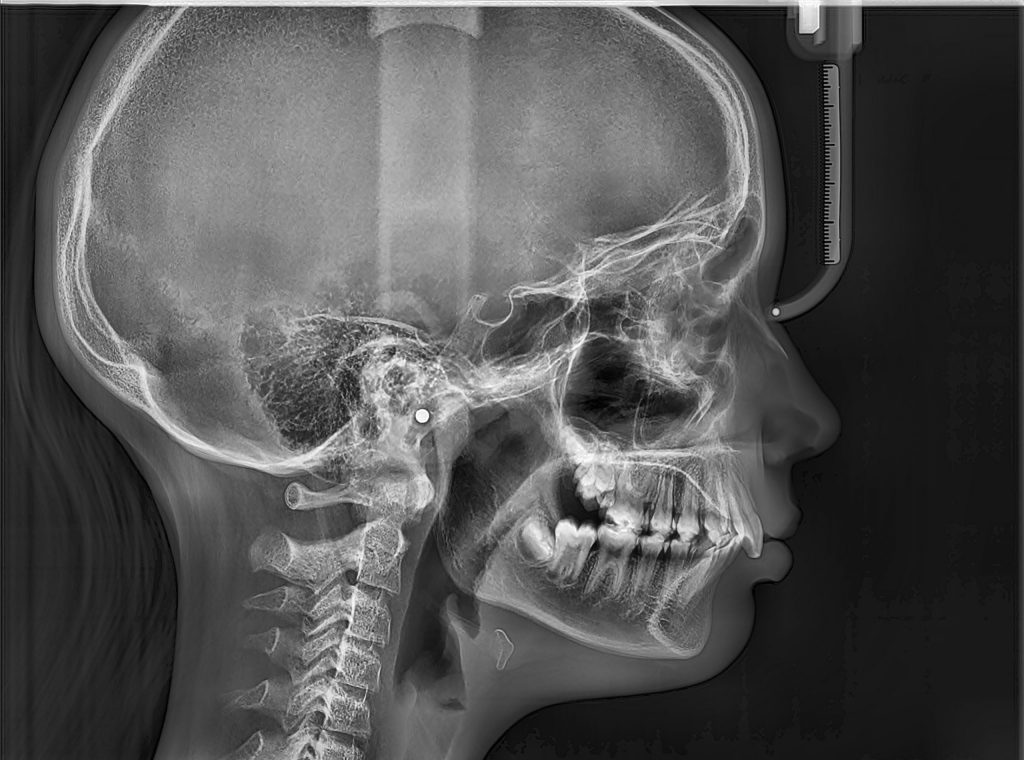

2. ΠΛΑΓΙΑ ΚΕΦΑΛΟΜΕΤΡΙΚΗ ΑΚΤΙΝΟΓΡΑΦΙΑ

Η πλάγια κεφαλομετρική ακτινογραφία είναι μια πλάγια ακτινογραφία του κρανίου.

Συνηθέστερα ζητείται από τον ορθοδοντικό και χρησιμοποιείται για τον ακριβή προσδιορισμό αποστάσεων και γωνιών μεταξύ ανατομικών σημείων των οστών των γνάθων και των μαλακών μορίων του προσώπου, προκειμένου να αξιολογηθεί η πορεία ανάπτυξης των οστών του σπλαχνικού κρανίου και των γνάθων.

Η λήψη της είναι γρήγορη (διαρκεί λίγα δευτερόλεπτα) και ανώδυνη.